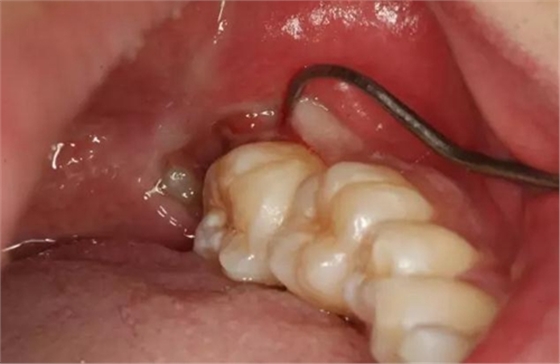

圖3.張口一指半的情況下,進行下牙槽神經(jīng)阻滯麻醉。

圖4.38頰側(cè)牙齦腫脹、探診出血

圖5探診分離牙齦